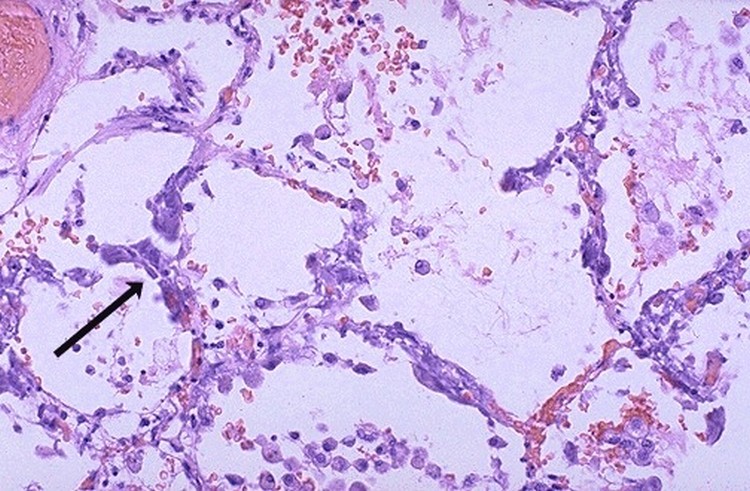

- Metastatik Kalsifikasyon

2- Metastatik kalsifikasyon; Bu tip kalsifikasyonda ise insan kanındaki kalsiyum miktarının artması (hiperkalsemi) ile normal dokularda kalsiyum tuzlarının birikimidir. Hiperkalsemi aynı zamanda distrofik kalsifikasyonu da şiddetlendirir. Metastatik kalsifikasyonda, dokularda görülmesi gereken kalsifikasyon dokuda değil de kanda görülmeye başlar. Vücutta en sık görüldüğü yerler böbrek borucukları, akciğer alveollerinin duvarları ve mide mukozasıdır. Beyinde, göğüs, karaciğerde kalsifikasyon olarak ta bilinmektedir.

Metastatik Kalsifikasyon